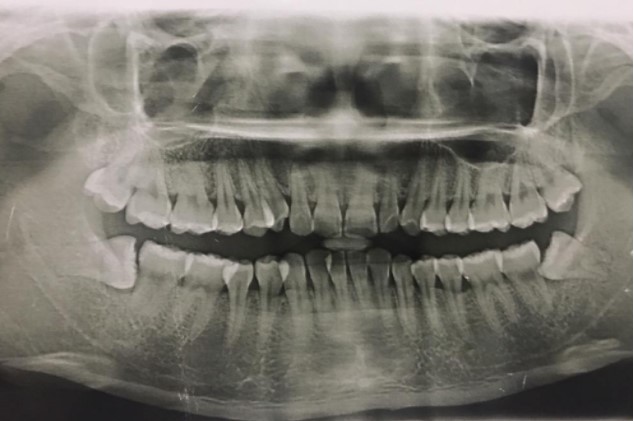

患者,男,38歲。上前牙變色1年,自述上前牙5年前受過外傷,唇側(cè)傾斜,檢查可見左上1牙冠變色,牙冠缺損近1/2,牙髓測試無反應(yīng),X線根尖片顯示患牙無明顯異常,全景片顯示雙側(cè)下頜智齒近中阻生,之前有發(fā)炎化膿病史,目前無咀嚼不適。口腔其余無異常。

檢查情況及X線片見下圖:

非主訴疾病的診斷依據(jù):X線全景片顯示雙側(cè)下頜智齒近中阻生。